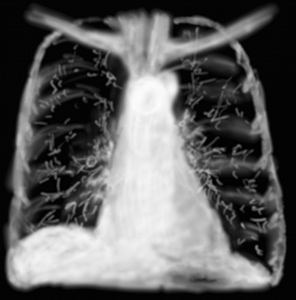

RP métastases

Certaines anomalies ont peu de traduction auscultatoire mais une radiographie très marquée, il en est ainsi de l’aspect en lâcher de ballons des métastases pulmonaires de cancer du sein, de la prostate, du rein, de la thyroïde.